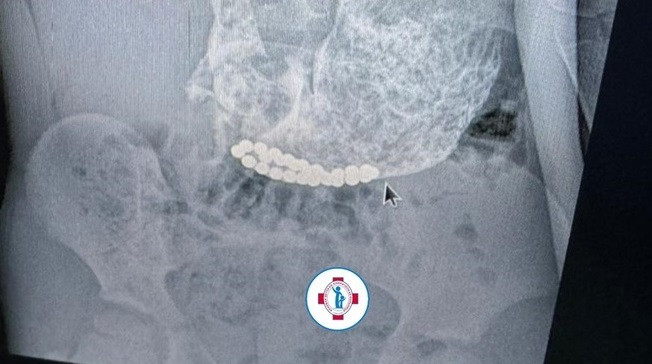

В третьем случае родители изначально не заметили, что малыш проглотил шарики. У ребенка началась частая рвота и взрослые обратились в медучреждение. Специалисты сделали юному пациенту рентген брюшной полости, который выявил наличие инородных тел в тонком кишечнике.

Ребенка сразу же направили в Краевую детскую больницу, где его экстренно прооперировали. Сейчас малыш продолжает лечение, сообщили в КДКБ.